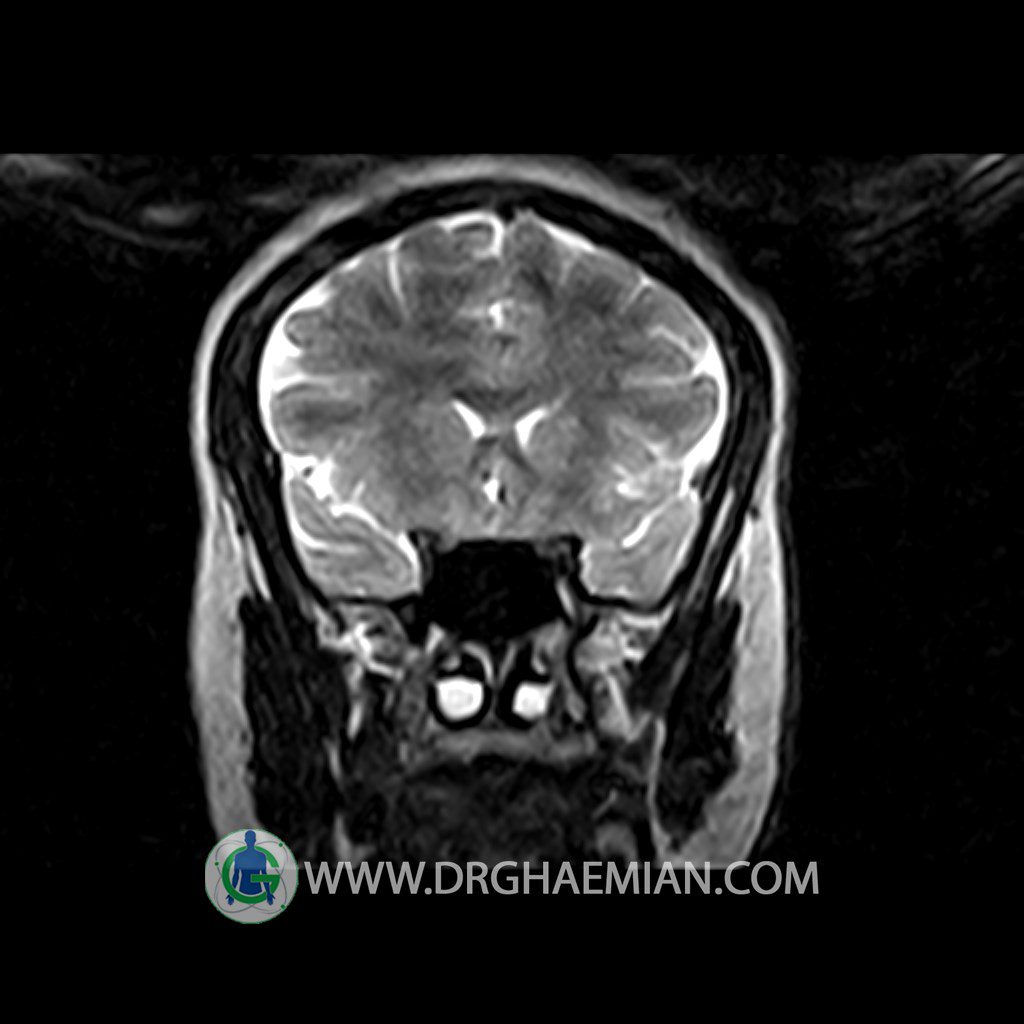

Technique: Axial , coronal T1 , Axial , coronal , sagittal T2 , Axial, coronal T1 post Gd & 64 dynamic thin coronal slices.

– Extension of suprasella cistern to sella with thin pituitary gland in floor of sella ( partial empty sella )

is seen